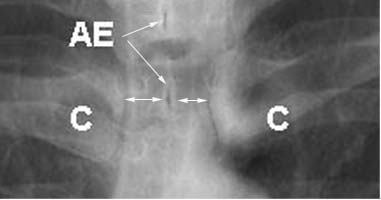

b) La radiografía frontal debe estar bien centrada, lo que se puede verificar comprobando que los extremos esternales de ambas clavículas (C) equidisten de la sombra central de las apófisis espinosas vertebrales (AE).

PLACA 1b detalle